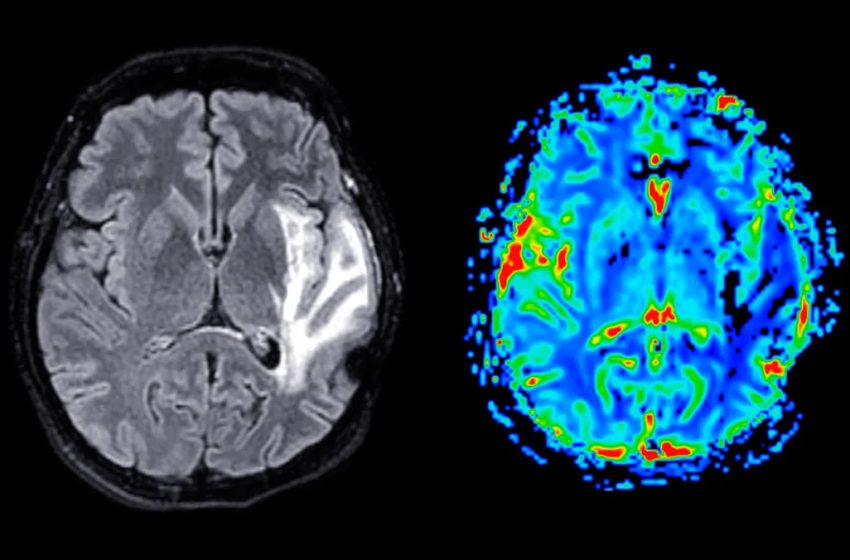

For decades, scientists have known what Alzheimer’s disease looks like. According to the National Institute on Aging, scientists find sticky amyloid plaques, tangled tau proteins, and atrophy (shrinking in the brain) in patients with Alzheimer’s disease,

The two proteins at the center of this discovery are called the NMDA receptor and the TRPM4 ion channel. Under normal, healthy conditions, the NMDA receptor is actually one of the brain’s most important tools. It helps neurons communicate with each other and plays a critical role in learning and memory. However, when NMDA receptors interact with TRPM4 channels outside of their usual locations, they form a harmful connection that changes how the receptors behave and leads to damage inside the cell. The researchers themselves describe this harmful combination as a “death complex.” When it forms, it starts a chain of events that leads to the death of nerve cells, ultimately contributing to the cognitive decline that defines Alzheimer’s disease.

The NMDAR/TRPM4 death complex is responsible for toxic signaling of glutamate, which has been implicated in Alzheimer’s disease development. A study published in Molecular Psychiatry found a significant increase in this complex’s formation in the brains of Alzheimer’s mice. The sicker the brain, the higher the levels appeared. That correlation alone is a significant finding.